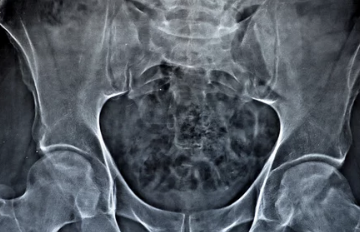

- X-ray: 뼈의 상태를 확인합니다.

- MRI: 연골, 인대, 근육 등의 상태를 확인합니다.

- CT: 뼈와 관절의 상세한 영상을 확인합니다.